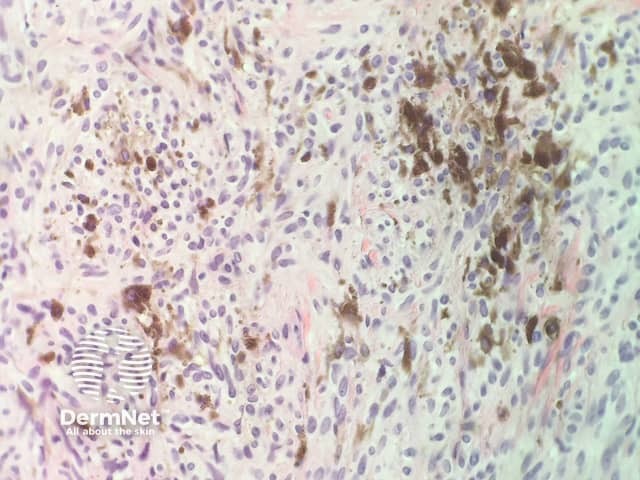

In combined trichoepithelioma and cellular blue naevus, the histopathology shows a fairly well-circumscribed biphasic dermal proliferation involving the full thickness of the dermis and shows tongues of rounded tumour fronts (figure 1). The tumour is composed of intimately mixed populations of melanocytes and basaloid cells. The basaloid cells anastomose in a lace-like pattern and form horn cysts focally (figure 2,3). The follicular component is surrounded by a prominent stroma, which is condensed around the basaloid islands as hair papilla-like structures. The melanocytic component consists of islands of plump spindled cells with abundant pale cytoplasm and minimal pigment and rarer slender dendritic melanocytes with heavy melanin pigmentation (figure 4).

Figure 4

The follicular and melanocytic components stain strongly with p63 and S100, respectively, and there is no cross-over of staining.